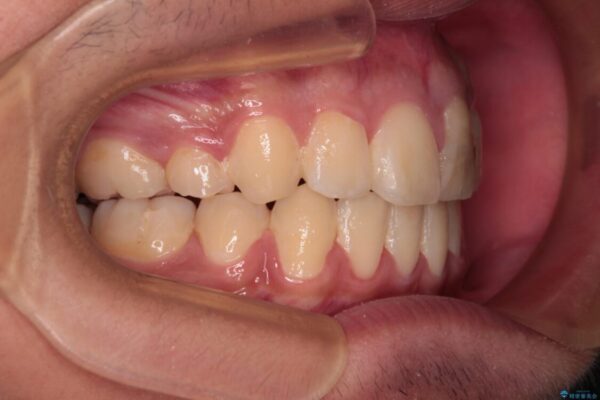

治療前

• 膨らんだ口元 ワイヤー装置での抜歯矯正 治療前画像